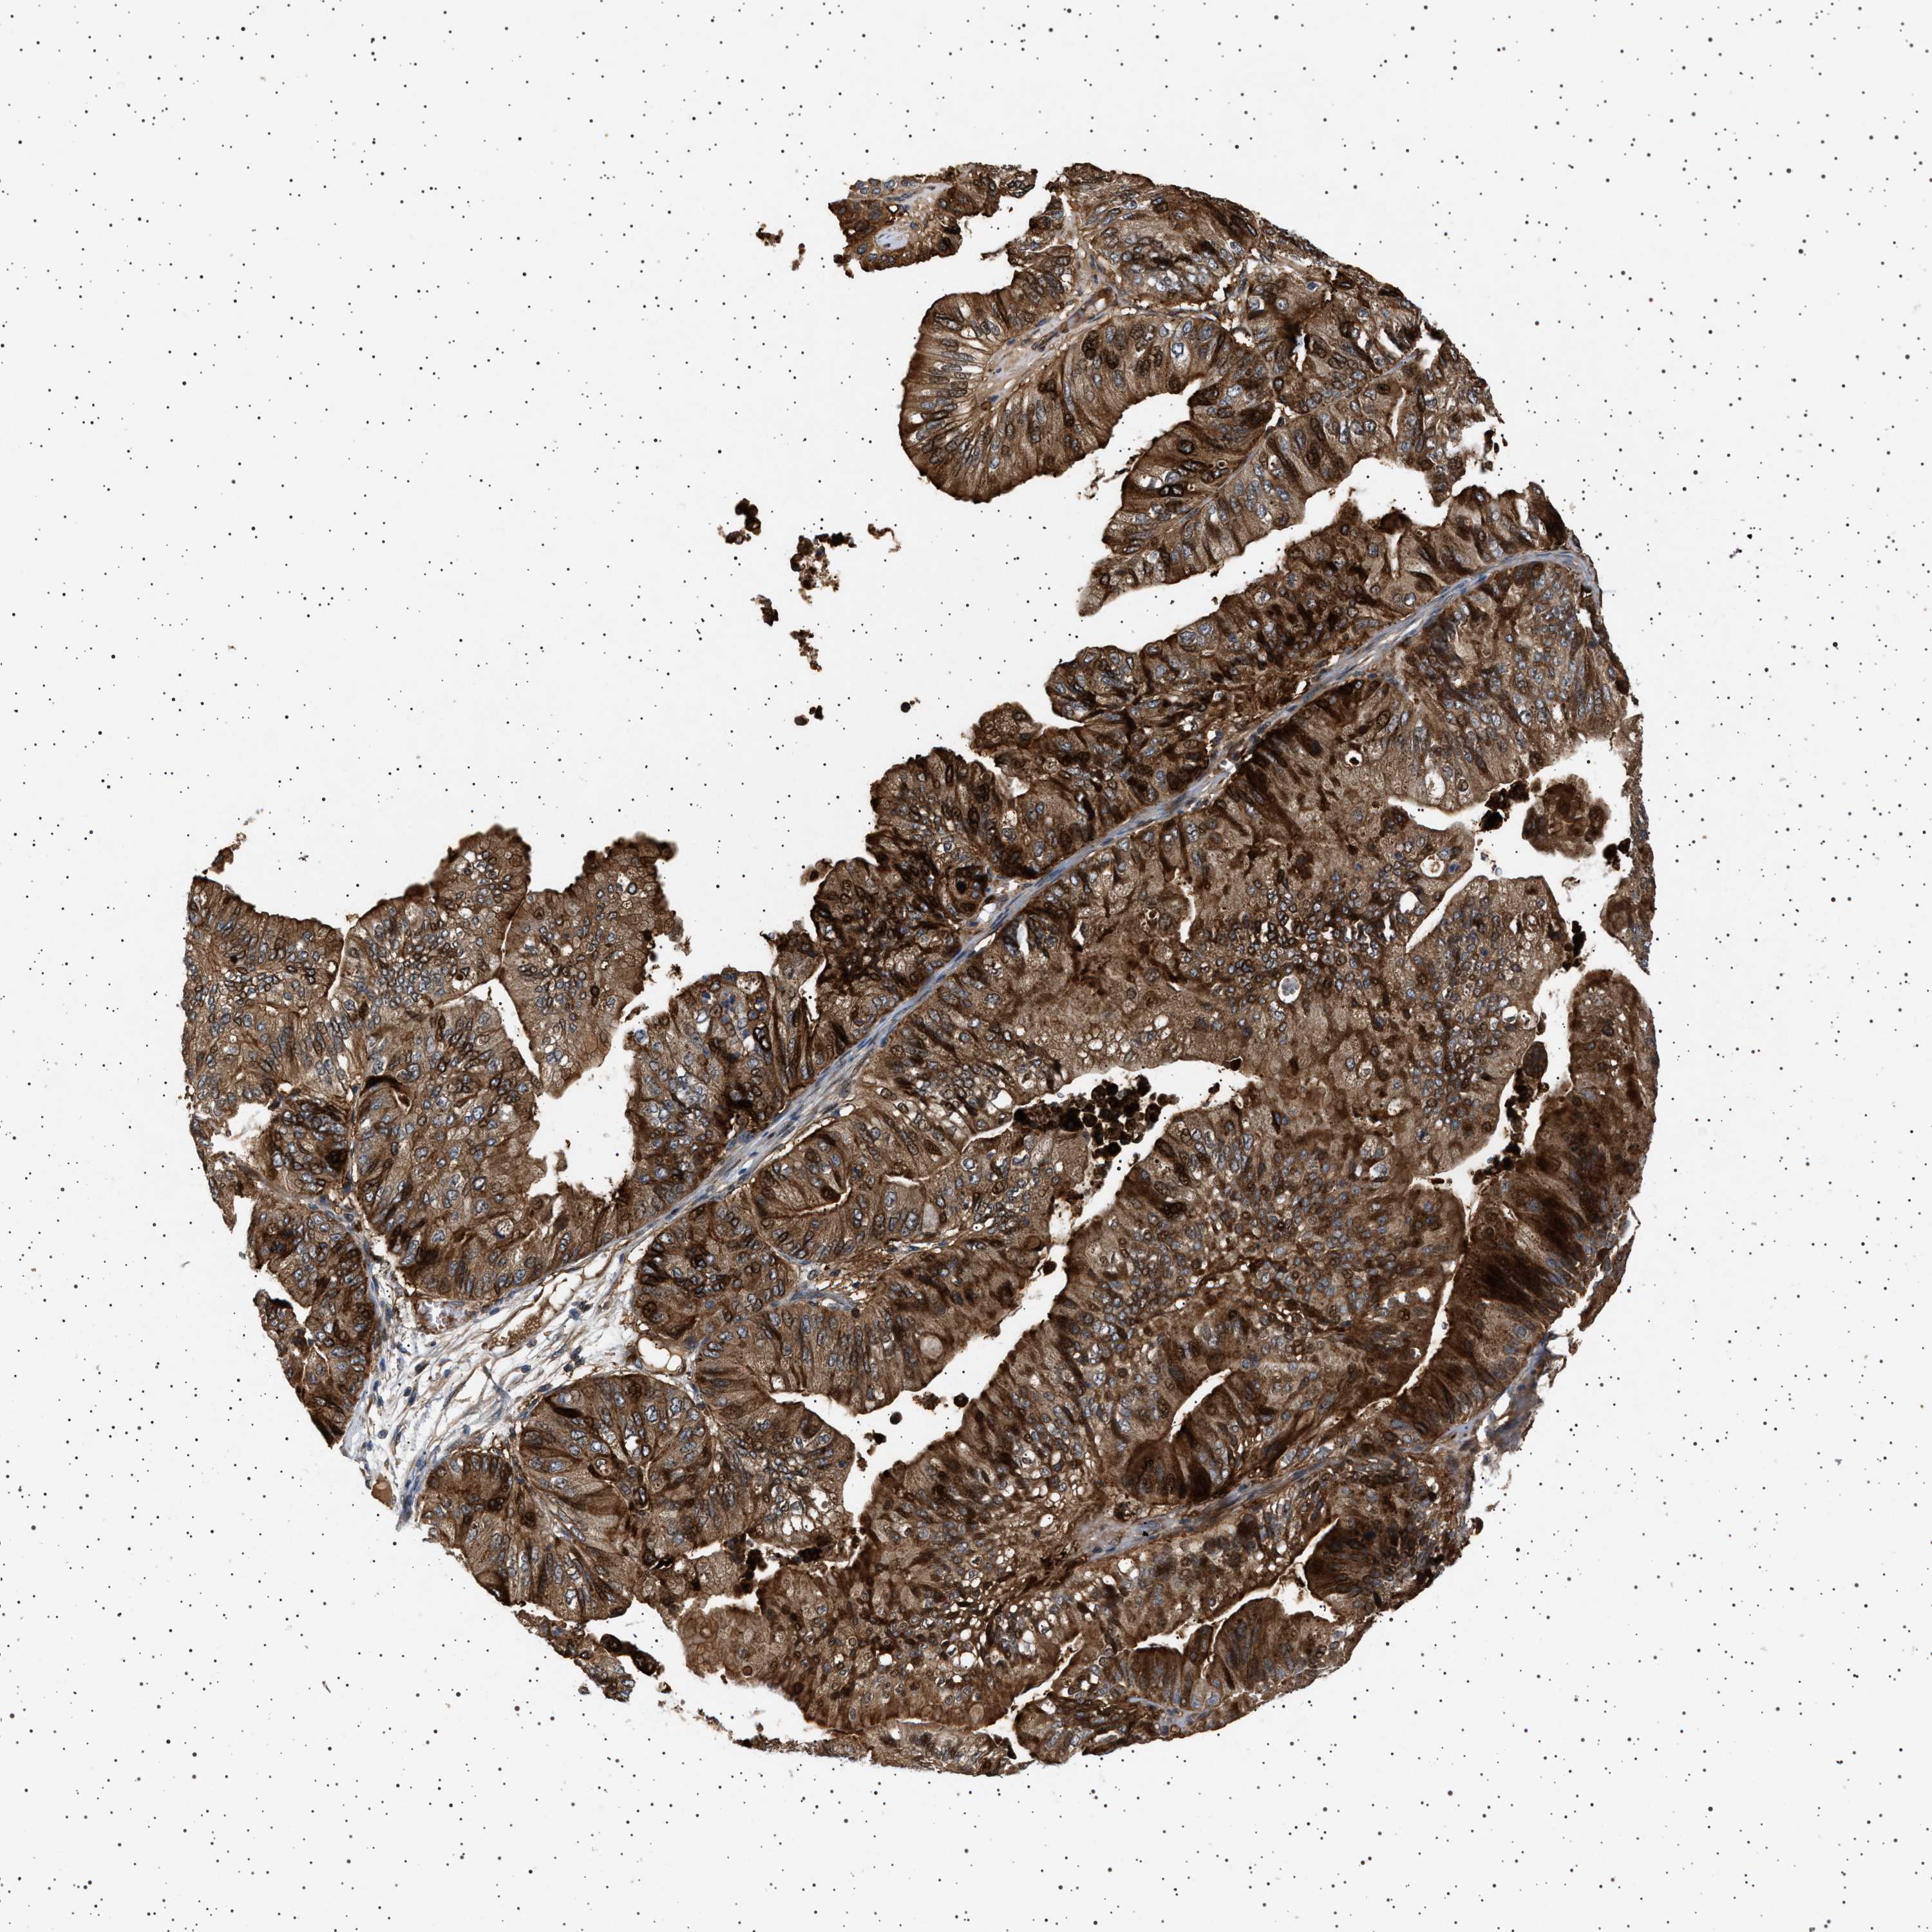

OVARIAN CANCER - Protein expressioni

A mouse-over function shows sample information and annotation data. Click on an image to view it in a full screen mode. Samples can be filtered based on level of antibody staining by selecting one or several of the following categories: high, medium, low and not detected. The assay and annotation is described here.

Note that samples used for immunohistochemistry by the Human Protein Atlas do not correspond to samples in the TCGA dataset.

Antibody stainingi

Antibody staining in the annotated cell types in the current human tissue is reported as not detected, low, medium, or high, based on conventional immunohistochemistry profiling in selected tissues. This score is based on the combination of the staining intensity and fraction of stained cells.

Each image is clickable and will lead to virtual microscopy that enables deeper exploration of all samples and also displays staining intensity scores, fraction scores and subcellular localization as well as patient and tissue information for each sample.

Antibody HPA020870

Antibody CAB010890

Carcinoma, endometroid